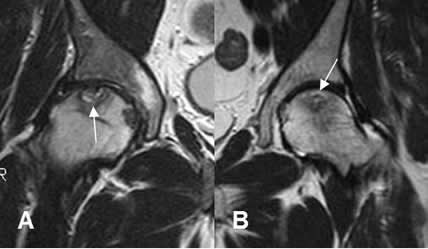

Fig 134. Osteonecrosis.

A y B: RM coronal en T2. Aunque no son pacientes con trauma, se muestran cambios por osteonecrosis. Signo del doble halo con reborde hiperintenso en T2, específico de esta patología.